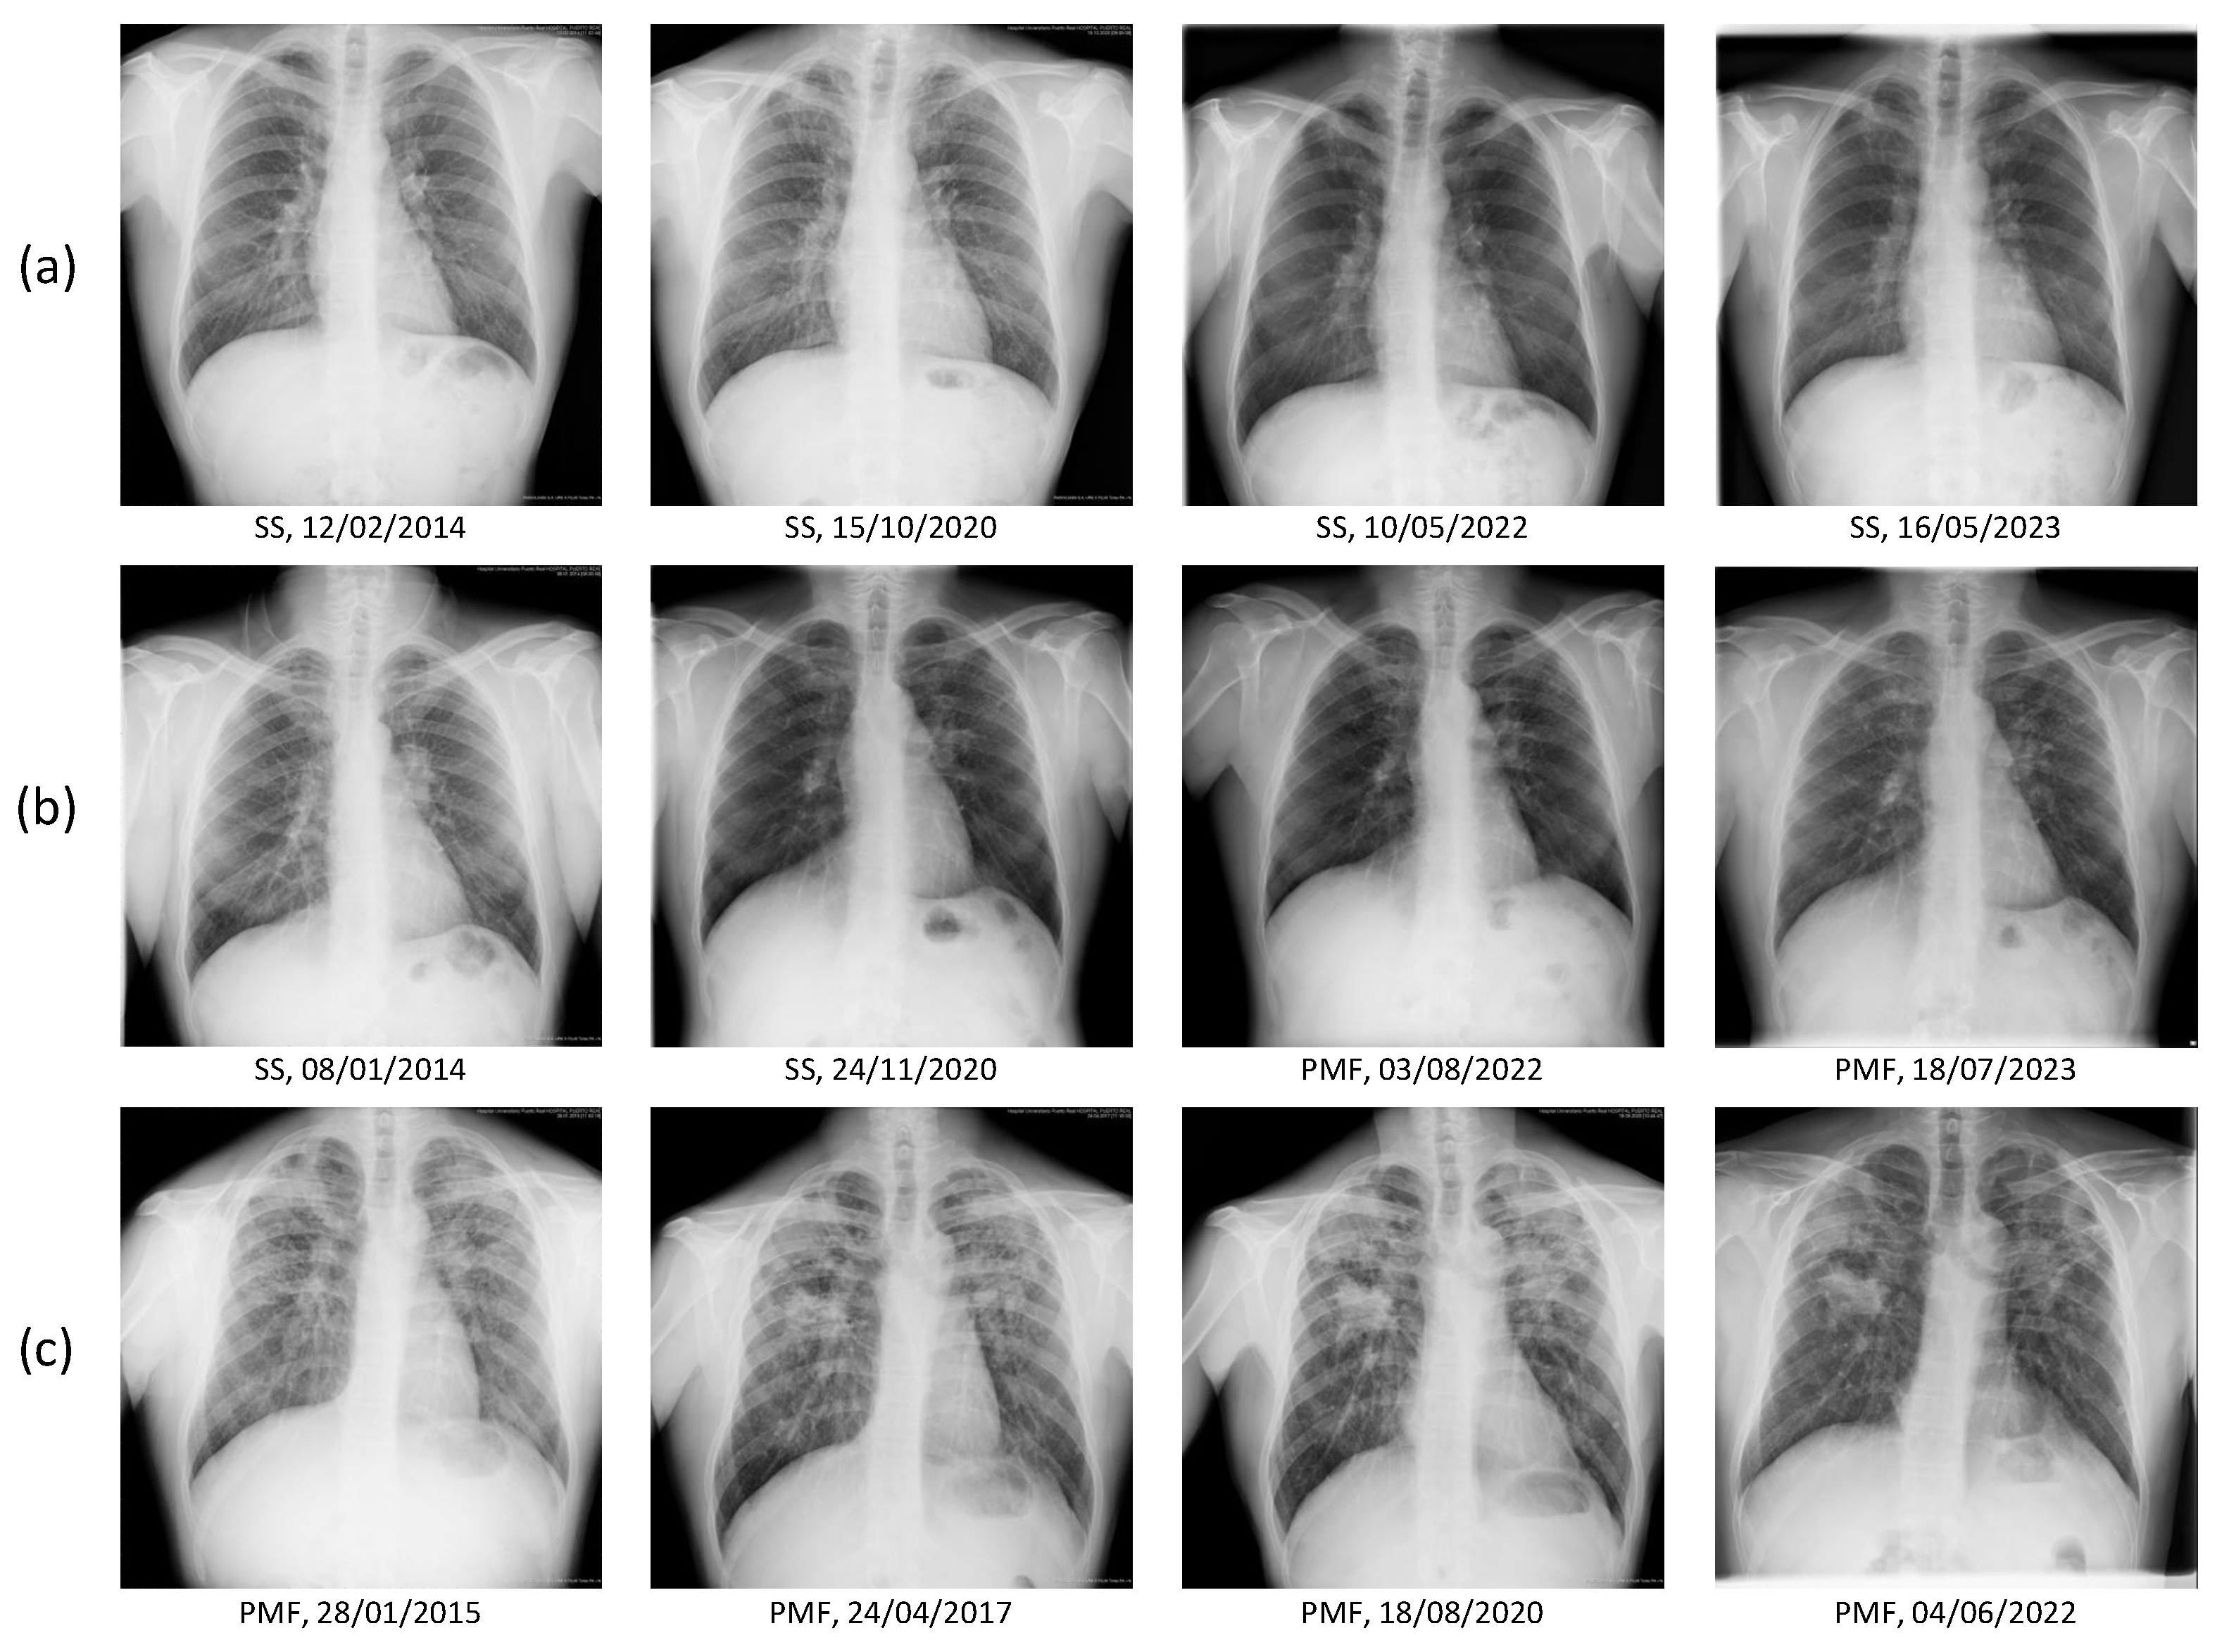

3.2. Ablation Study: Justification of Image Segmentation Method